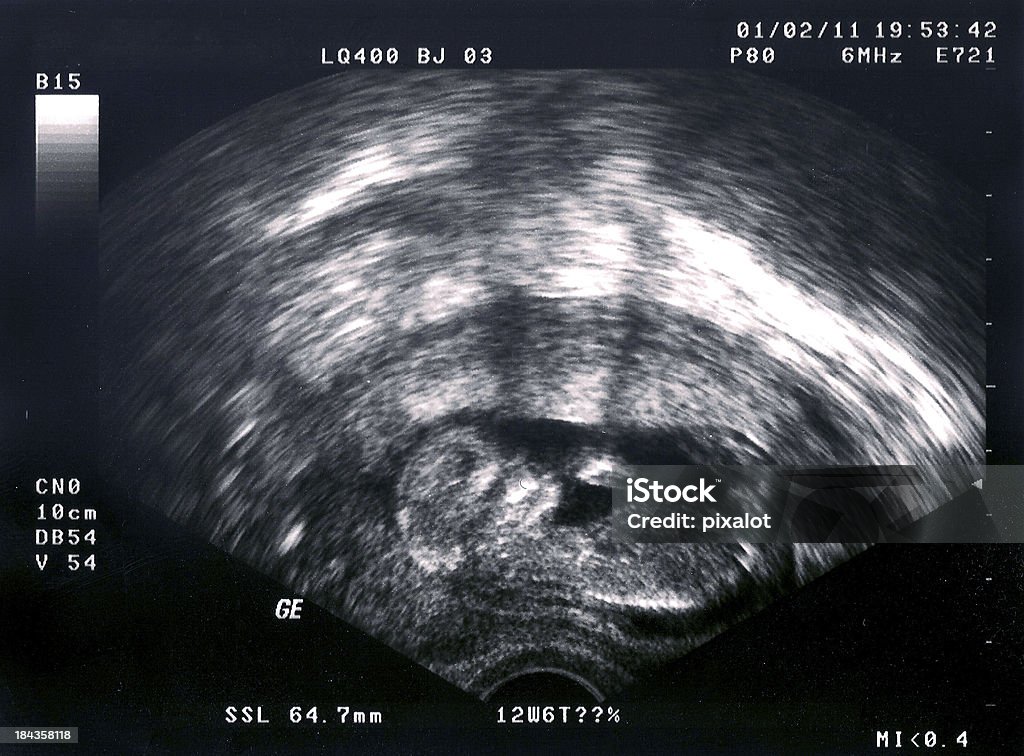

УЗИ диагностика гемоперитонеума

Раздел: Образы и смыслы